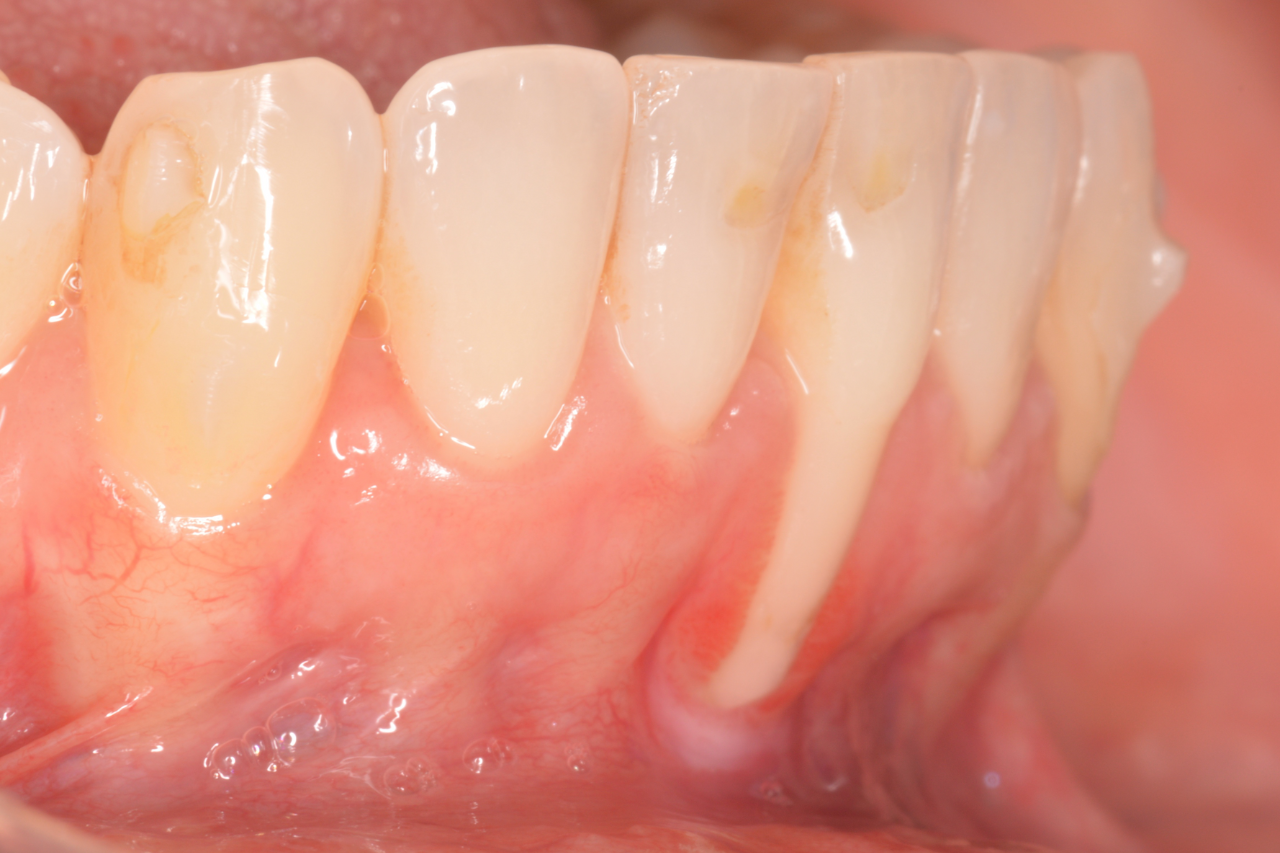

Hortzoien atzeraldia, hortzoietako ertzak bere posizio arruntetik (erroaren eta hortzaren arteko muga) desplazamendu bat jasaten duen prozesua da, sustraiaren zati bat bistan utziz.

Erroak estalita egon behar du, beraz, bistan dagoenean, arazo hauek sor ditzake:

- Hortzen sentikortasuna

- Erro higadura

- Erroko txantxar gehiago

- Hortzak gehiago mugitzea

- Mina eta inflamazioa garbitzean

- Arazo estetikoak